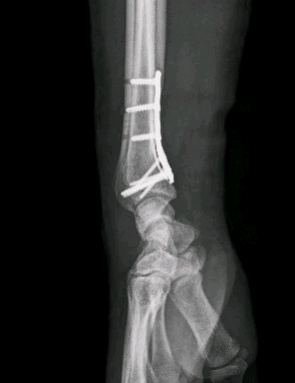

Em regra, as fracturas articulares ou não alinhadas devem ser submetidas a tratamento cirúrgico.

O tratamento tem como objectivo restabelecer a anatomia dos ossos fracturados; é na grande maioria dos casos colocada uma placa e parafusos para manter o alinhamento correcto após a redução.